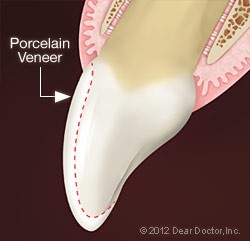

لامینت سرامیکی (ونیر سرامیکی) شامل یک پوسته نازک سرامیکی ( چینی) به قطر 0.5 - 0.6 میلیمتر است که دو برابر ضخامت یک پوسته تخم مرغ است وبه کمک انواع باندهای رزینی، روی دندان چسبانده می شود که می توان آن را توسط بلوک های کد کم یا توسط پرس سرامیکی و یا توسط پودرگذاری توسط تکنسین لابراتوار، ساخت.

در مواردی نظیر بد رنگیها و یا تغییر رنگ شدید دندان ها، منظم نمودن دندانها، بستن فضاهای بین دندانی، تغییر شکل دندانها، تغییر اندازه دندانها و ... می توان از این لامینت های سرامیکی (ونیرهای سرامیکی) یا از لامینت های کامپوزیتی (ونیرهای کامپوزیتی) استفاده کرد.

لامینتهای سرامیکی مقاومت بیشتری نسبت به کامپوزیتی دارند همچنین ثبات رنگ در لامینتهای سرامیکی بیشتر است و اصولا ظاهر زیباتری دارند. لامینتهای کامپوزیتی ثبات رنگ کمتری دارند و مزیت اصلی آنها نسبت به لامینتهای سرامیکی، قیمت ارزانتر و تراش کمتر آنهاست است.